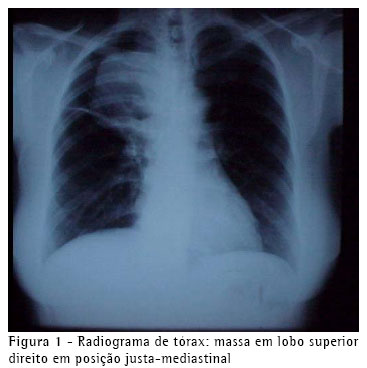

Uma paciente com 52 anos, previamente hígida, apresentou-se com quadro de hemoptise não maciça. Negava história de tuberculose ou tabagismo. Ao exame físico encontrava-se pálida, sem linfonodos palpáveis, e com ausculta pulmonar diminuída à direita. O radiograma de tórax (Figura 1) mostrava uma massa pulmonar com limites indefinidos, justamediastinal, em lobo superior direito.